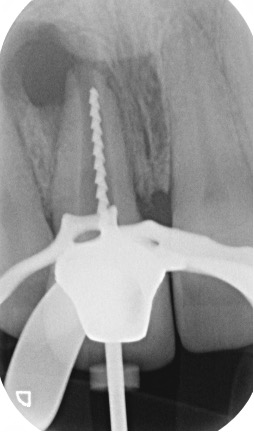

Separated instruments

Separated instruments can occur during root canal treatment. These may be able to bypassed or removed to allow completion of the root filling.